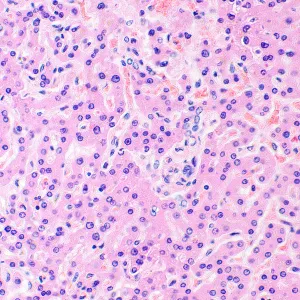

Микроскоп исследовательского класса. Предназначен для наблюдения прозрачных и полупрозрачных биологических образцов в виде мазков и срезов в проходящем свете в светлом поле. Установка опциональных компонентов позволит использовать методы темного поля, фазового контраста, дифференциально-интерференционного контраста, люминесценции и поляризации.

Наблюдения прозрачных и полупрозрачных образцов в светлом поле в проходящем свете Тринокулярная насадка с вертикальным тубусом для установки цифровой камеры и изменением угла наклона; переключение светового потока 0/100, 100/0 или 80/20 Моторизированное револьверное устройство – смена рабочего объектива происходит по нажатию кнопки; удобная панель для дистанционного управления револьвером Осветитель проходящего света – экономичный светодиод 3 Вт со сроком службы до 50 000 часов Освещение по Кёлеру в проходящем свете, моторизированный конденсор с откидной линзой Интеллектуальная система управления освещением – автоматический выбор яркости при смене рабочего объектива Предметный столик с пластиной из сапфирового стекла и с длинной ручкой управления для удобной работы Широкая линейка дополнительных аксессуаров Комплектация: